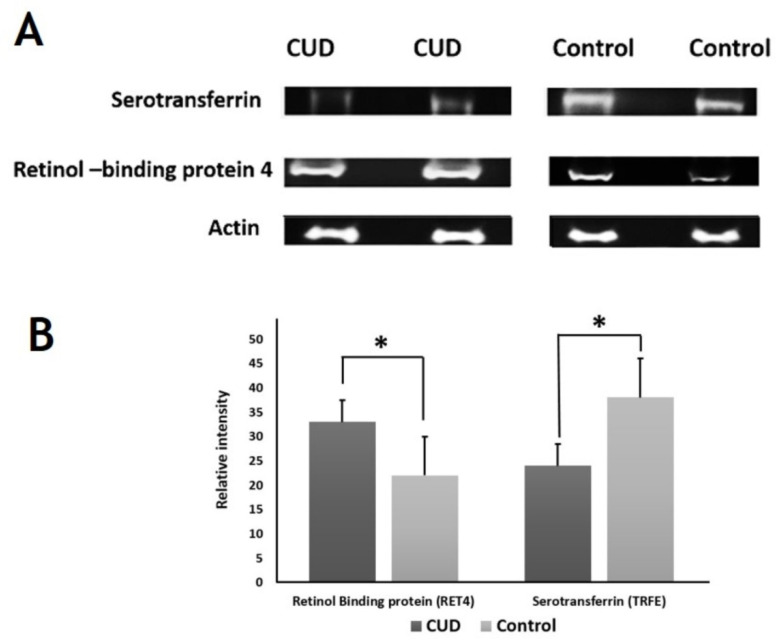

2.6. Immunoblotting Confirmation of Changes in Selected Proteins

Immunoblot assay confirmed the expression of the selected proteins that were differentially abundant by 2D-DIGE analysis (Figure 7). The proteins selected for confirmation were serotransferrin and retinol-binding protein 4. Immunoblots revealed that the serum protein expression of serotransferrin and retinol-binding protein 4 were decreased and increased, respectively, in CUD group as compared with control group (p ≤ 0.05). To normalize the immunoblot data, β-actin was used in the present study as a housekeeping protein (Figure 7A,B).